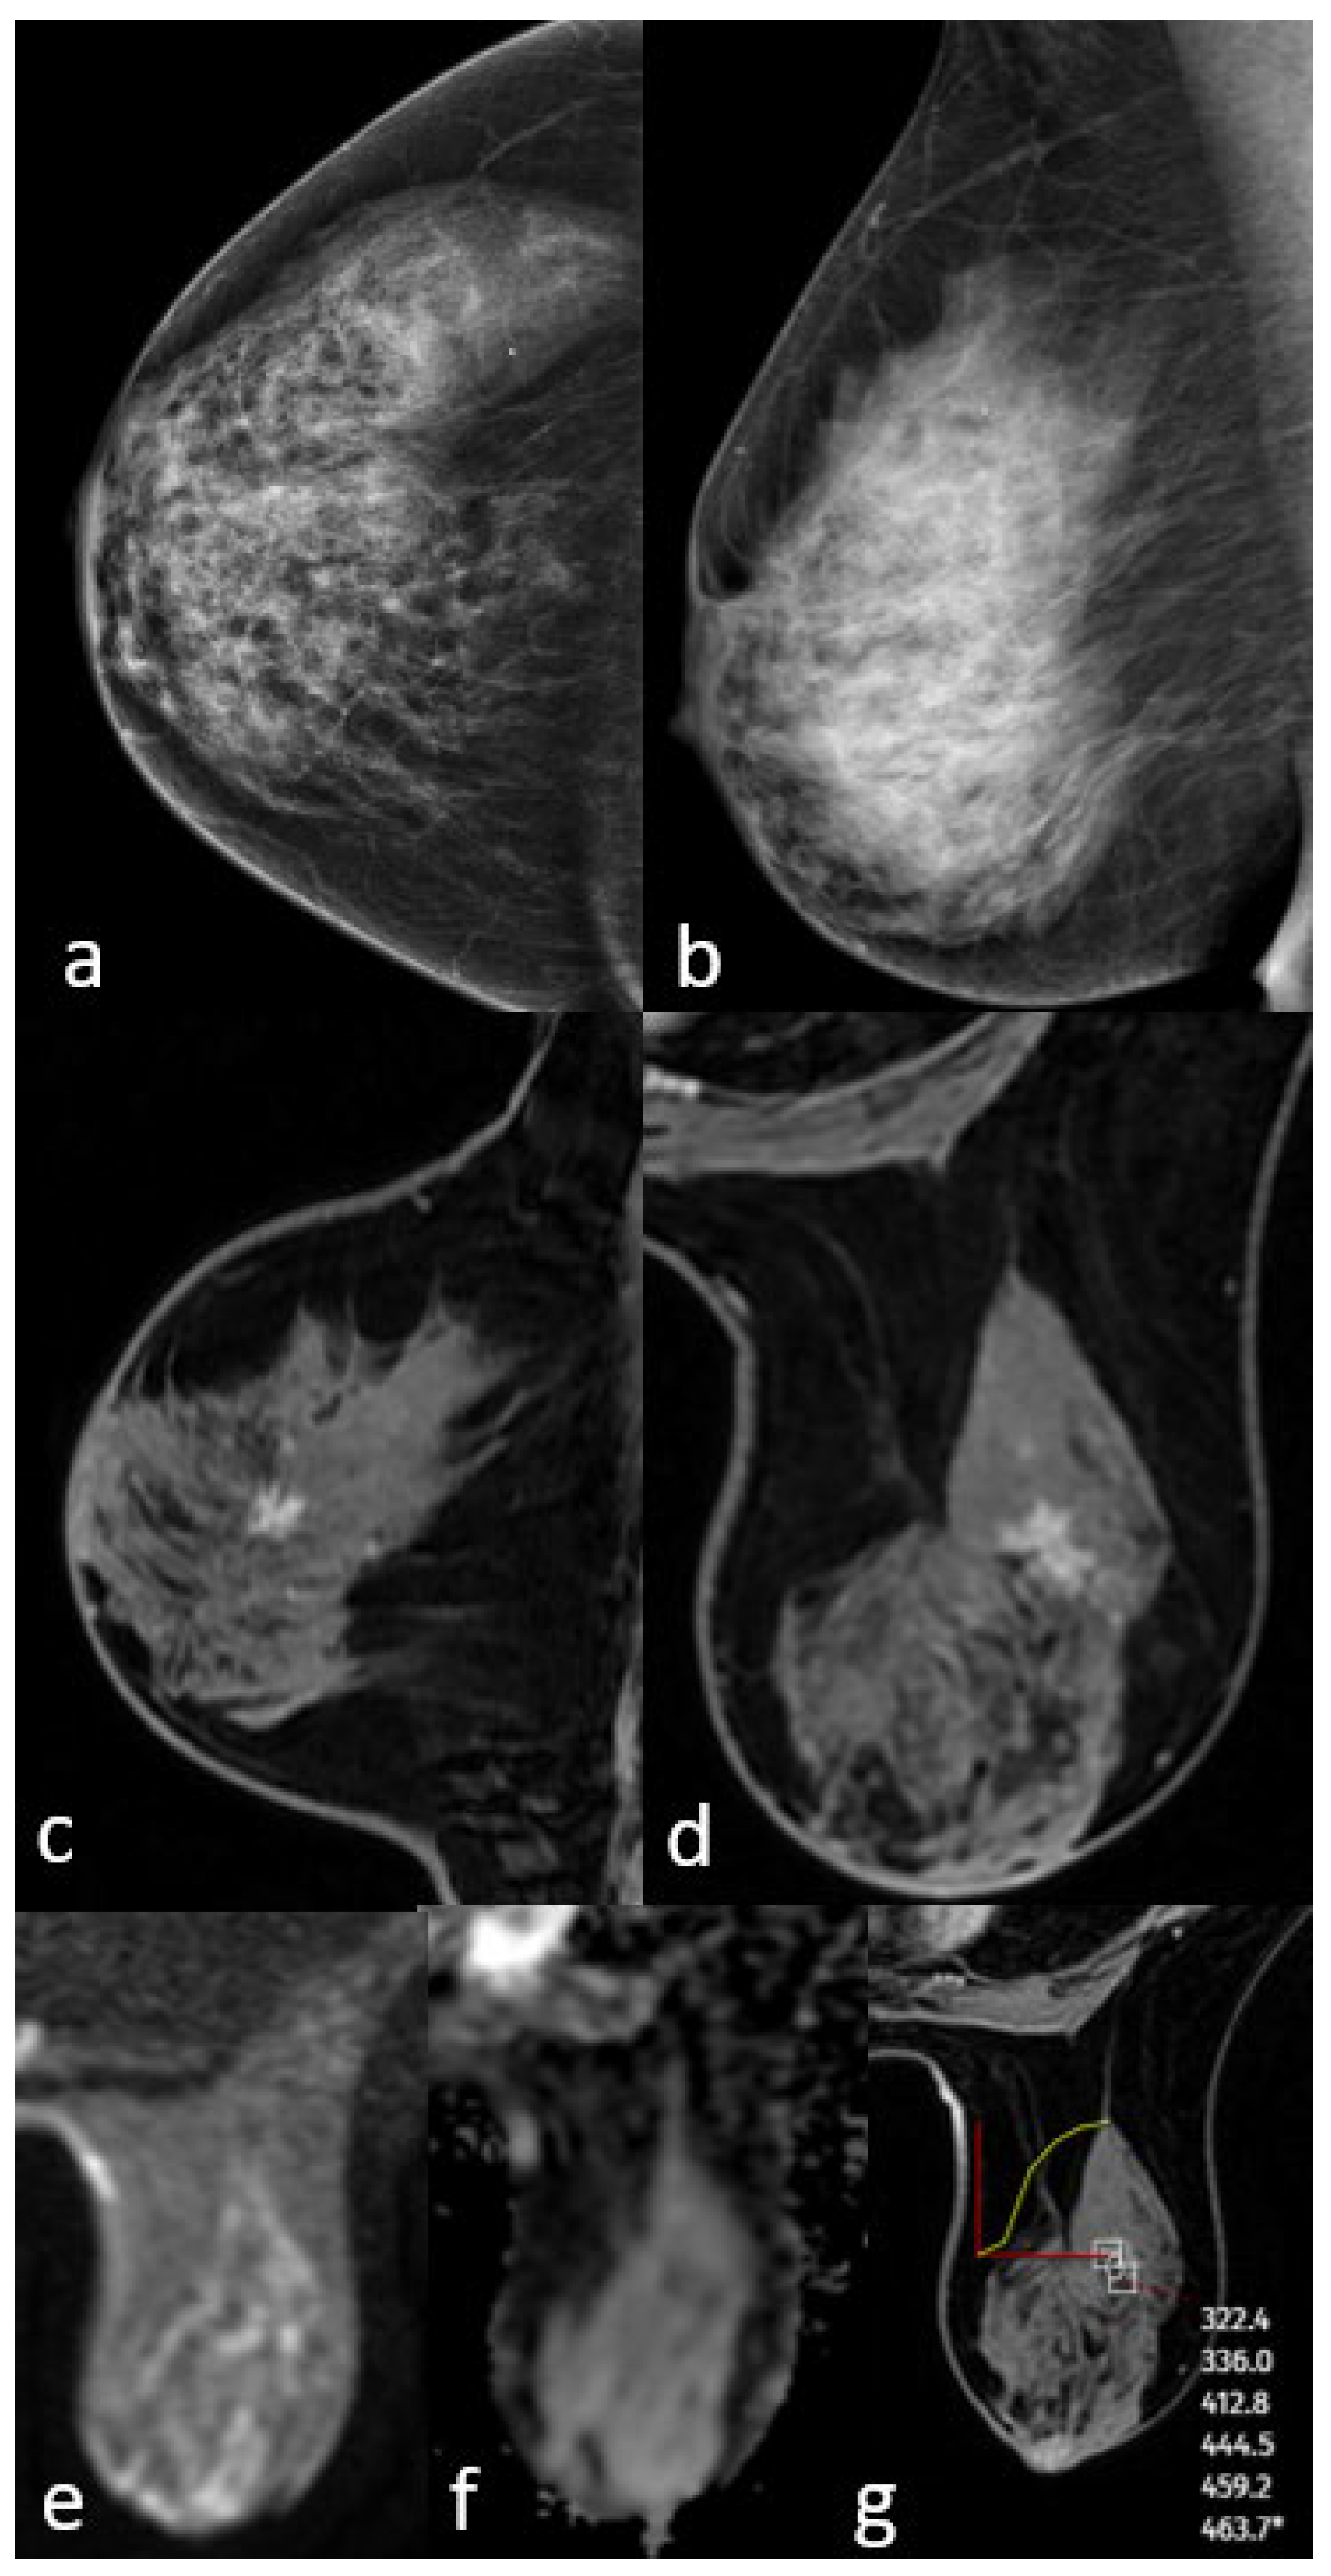

3.1. Mammographic Findings

3.2. Magnetic Resonance Imaging Findings